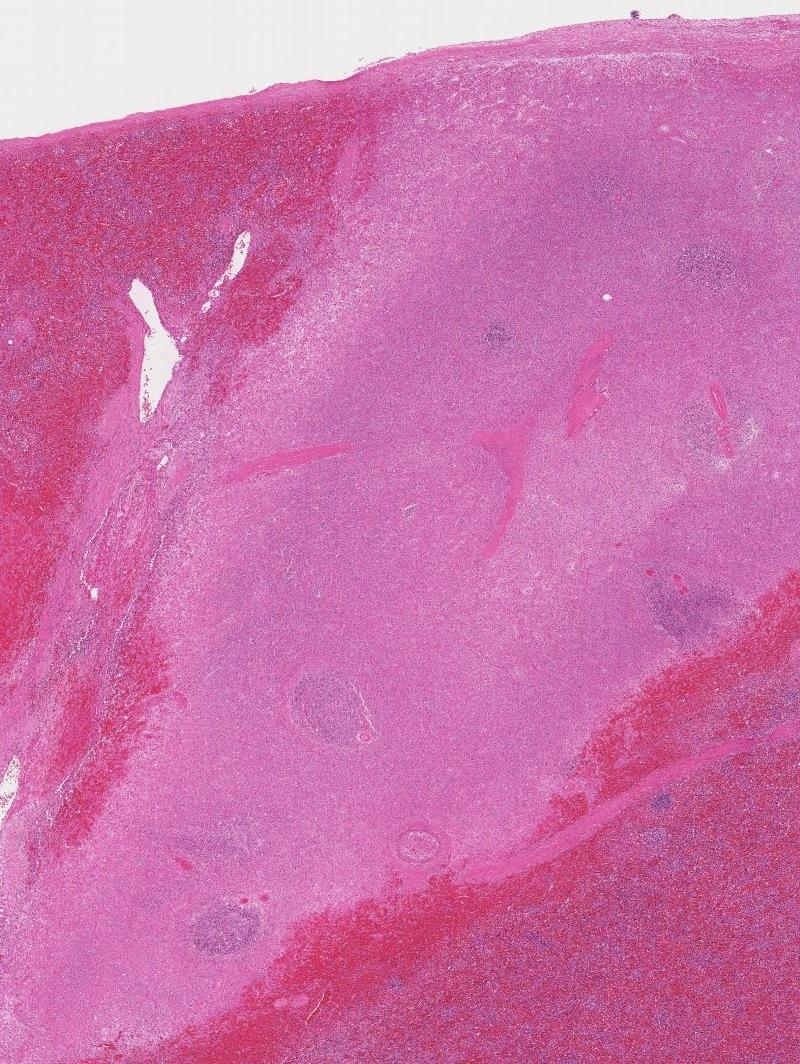

Micro

Pathology